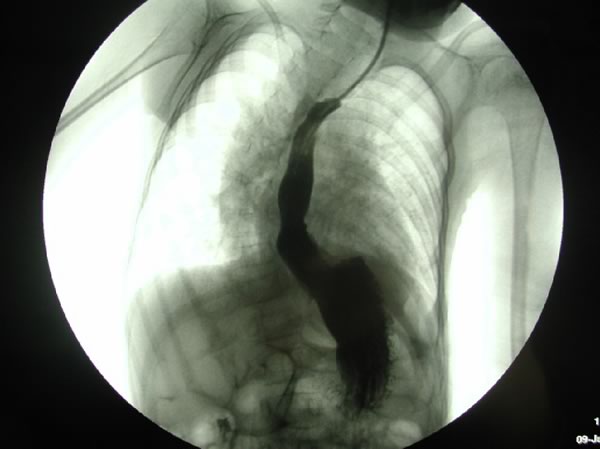

- Deglutogramma e transito esofageo con pasto di bario: evidenzia il passaggio del bolo di mezzo di contrasto dall’orofaringe allo stomaco, e l’eventuale reflusso (Figura 2), mettendo in luce anche alterazioni anatomiche (ernia iatale). Offre inoltre la possibilità di studiare il transito oltre il piloro. Il difetto dell’esame è quello di “fotografare” ciò che accade in “quel momento”, ed in questo senso la sensibilità per RGE è di fatto stimata intorno 50%. Nei bambini portatori di gastrostomia percutanea per via endoscopica (PEG) il contrasto è iniettabile attraverso il “bottone” di gastrostomia (Figura 2 bis).